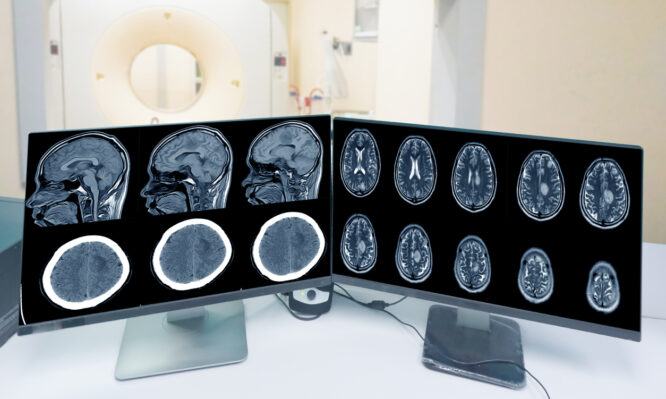

Η ατμοσφαιρική ρύπανση συνδέεται με κοινούς όγκους του εγκεφάλου

Αρκετοί διαφορετικοί τύποι ατμοσφαιρικών ρύπων, συμπεριλαμβανομένης της σωματιδιακής ρύπανσης και του διοξειδίου του αζώτου, φαίνεται να αυξάνουν τον κίνδυνο εμφάνισης μηνιγγιωμάτων – όγκων που σχηματίζονται στα στρώματα του ιστού που καλύπτουν τον εγκέφαλο και τον νωτιαίο μυελό, ανέφεραν οι ερευνητές στις 9 Ιουλίου στο περιοδικό Neurology.